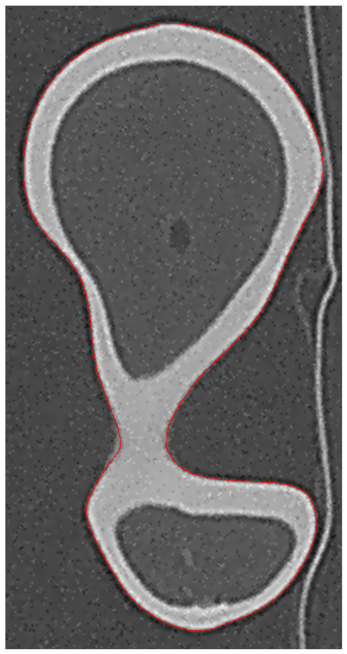

Two outputs may be produced after segmentation refinement (Fig. 2), a high-resolution point cloud model obtained directly from the interpolated image, and a down-scaled version of the high-resolution segmentation. The surface mesh model obtained from the point cloud will be referred as Point Cloud (PC) model. Since image refinement is performed independently in each image, the PC model is produce directly from a set of equally spaced contours by tiling the cloud points. The surface mesh of the down-scaled version was generated in Simpleware ScanIPTM v4.0𝑣4.0v4.0, with standard pre-smoothing and mesh refinement settings [49][50], and will be referred simply as ScanIP Mesh (SM) model. The segmentation pipeline was tested in noise-free and noisy images, corrupted with AWGN with a standard deviation of σNoise=10subscript𝜎𝑁𝑜𝑖𝑠𝑒10\sigma_{Noise}=10 HU. Fig. 5 shows the sub-stpng of the segmentation refinement process when applied to both noise-free and noisy images. The Hausdorff Distance (HD) and the Mean Symmetric Distance (MSD) [51] were applied to evaluate each segmentation outcome.

Figure 5: Segmentation refinement pipeline applied to the Dataset #1: in (a) the original image data without noise; in (b) the image data after de-noising with anisotropic diffusion and image deconvolution; in (c) image cropping and interpolation around the pre-segmented region; and in panel (d) the final segmentation contour superimposed over the pre-segmentation mask; in (e), (f), (g) and (h) image refinement is applied to the same image corrupted with AWGN

Fig. 6 shows the final PC model obtained from the segmentation of Dataset #1 and the comparison with the Nikon Metris LK𝐿𝐾LK V20𝑉20V20 gold standard, whereas Fig. 7 depicts the down-scaled segmentation within Simpleware ScanIPTM v4.0𝑣4.0v4.0 overlapped with reference surface. A close agreement between both PC and SM, and the gold standard is observed for both models. The agreement between the PC and SM model and the gold standard for all noise-free and noisy Datasets regarding the distance measures are summarized in Table II and Table III, respectively.

Figure 7: On left (a) the domain pre-segmentation and final segmentation after refinement for the Dataset #1, in the middle (b) the surface mesh generated with Simpleware ScanIPTM and the reference model, and the comparison between the two models (c)